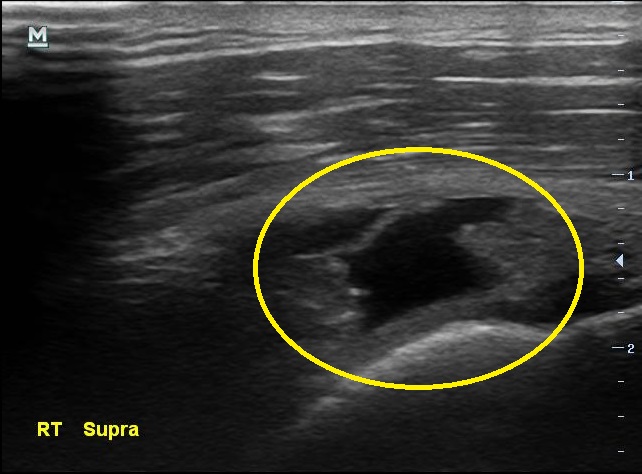

3개월만에 통증이 더 심해졌다고 찾아온 남자분, 검사 결과는 3개월전보다 더 악화 되었습니다.

초음파 검사 결과 3개월전에 비해 극상근 힘줄의 파열 정도가 더 심해져있습니다.

나 : 초음파 검사 결과가 더 나빠졌는데요...

나 : 초음파에서 이정도 소견이면..... MRI 촬영하고 필요하면 수술도 고려해보아야 할 정도네요